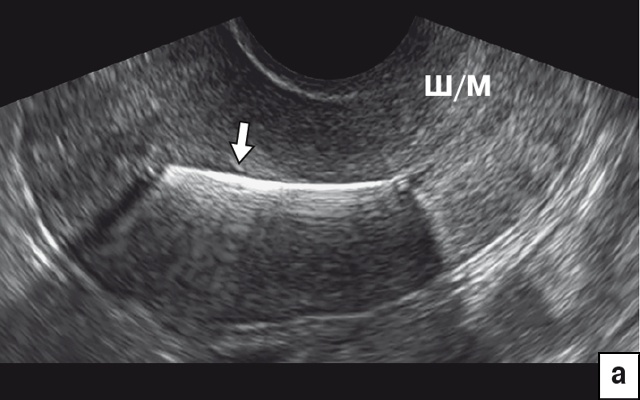

На рис. 2 отражена картина различных ВМС на среднесагиттальном срезе матки при 2D-УЗИ. Для всех Т-образных форм ВМС (включая Мирену) и Multiload стандартной картиной является визуализация гиперэхогенной линейной структуры в проекции полости (рис. 2а). В отличие от Т-образных, Multiload при исследовании в парасагиттальном сечении дает дополнительную специфическую ультразвуковую картину в виде 3–4 продольно расположенных одинаковых гиперэхогенных включений (рис. 2в). Также характерную картину на сагиттальном срезе дают кольцевидные ВМС в виде проксимальной короткой линейной структуры и дистальной отдельной точечной (рис. 2б) и петля Липпеса в виде 4–5 отдельных эхогенных фрагментов (рис. 2г). Кольцевидные ВМС и петля Липпеса в настоящее время практически вышли из употребления.

а) Гиперэхогенная картина стержня ВМС (стрелка) в проекции полости матки.